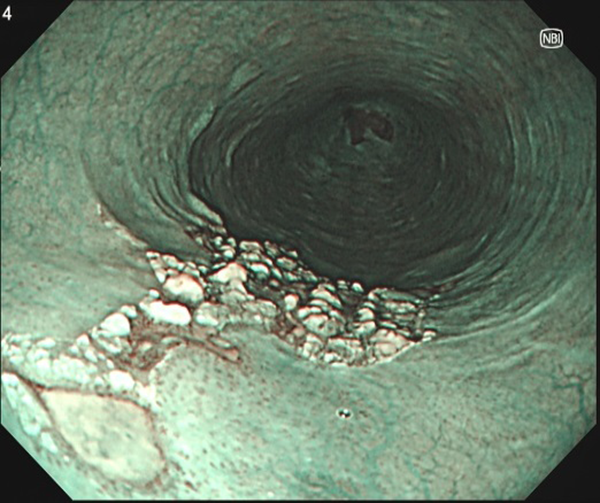

①下咽頭癌-1(経口拡大内視鏡)

1. 弱拡大 左下咽頭(左喉の奥)にNBI画像処理で茶色に見える小さな部分を認めます。

2. 強拡大 B1血管と呼ばれる周囲より太い血管が密集しているところが癌です。

鏡視下下咽頭悪性腫瘍切除術で治癒、径12×11mmの扁平上皮癌と診断されました。